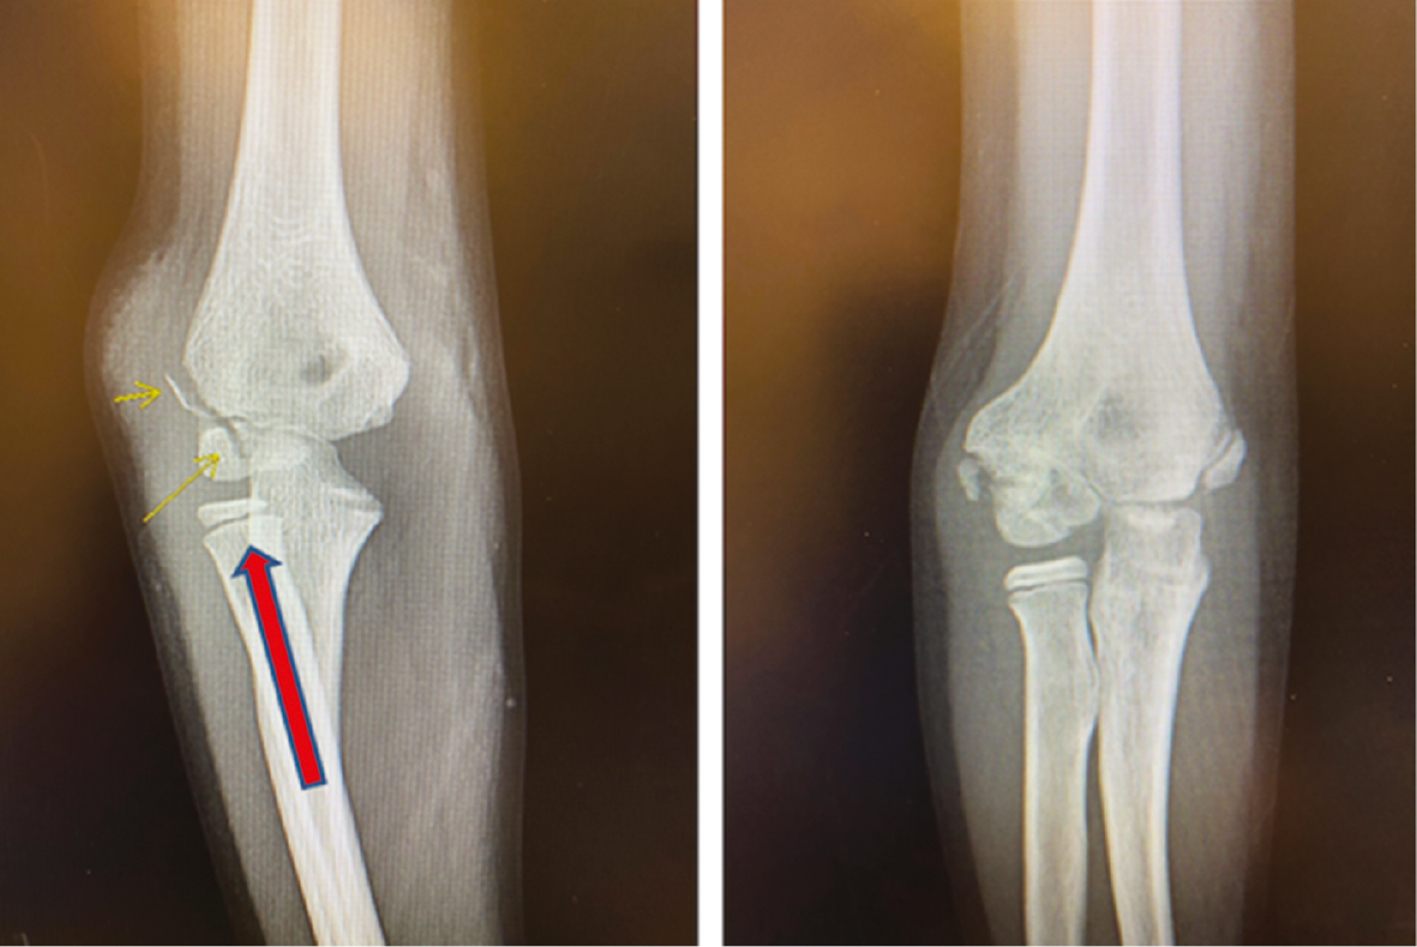

Rarely does a lateral condyle fracture result from an axial load in valgus that shears the lateral condyle proximally and always disrupts the articular surface (Figure 2). These are much harder to reduce closed and are more likely to require open reduction and internal fixation.

Figure 2. This intraarticular fracture (left) is likely a result of an axial load in valgus and can shear the lateral condyle off. Note the lateral elbow swelling. One year after closed treatment (right), the fracture has healed but is in slight cubitus varus. This would correspond to a Milch 1 fracture.